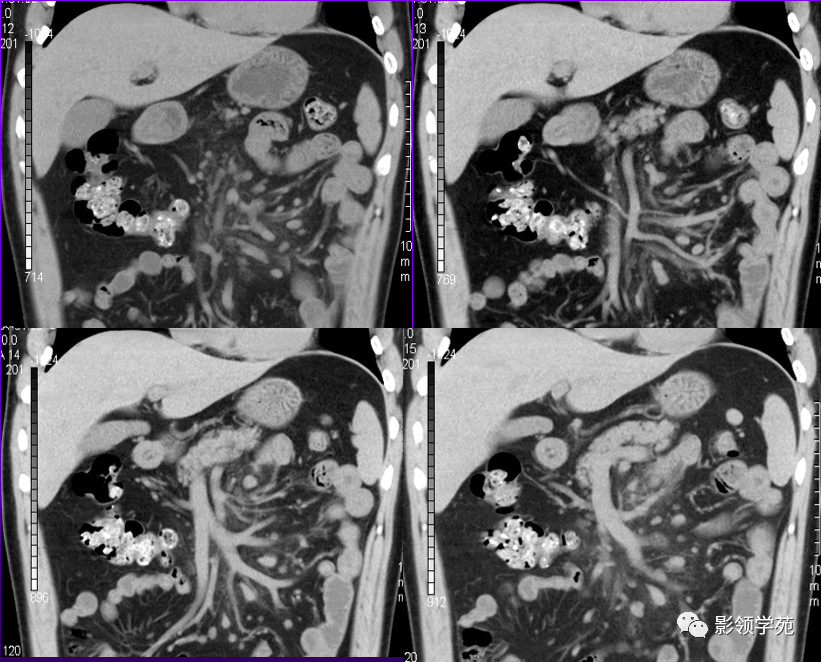

冠状面重建图象显示雾状肠系膜,内可见大小不等的结节影及散在纤维条缩影。